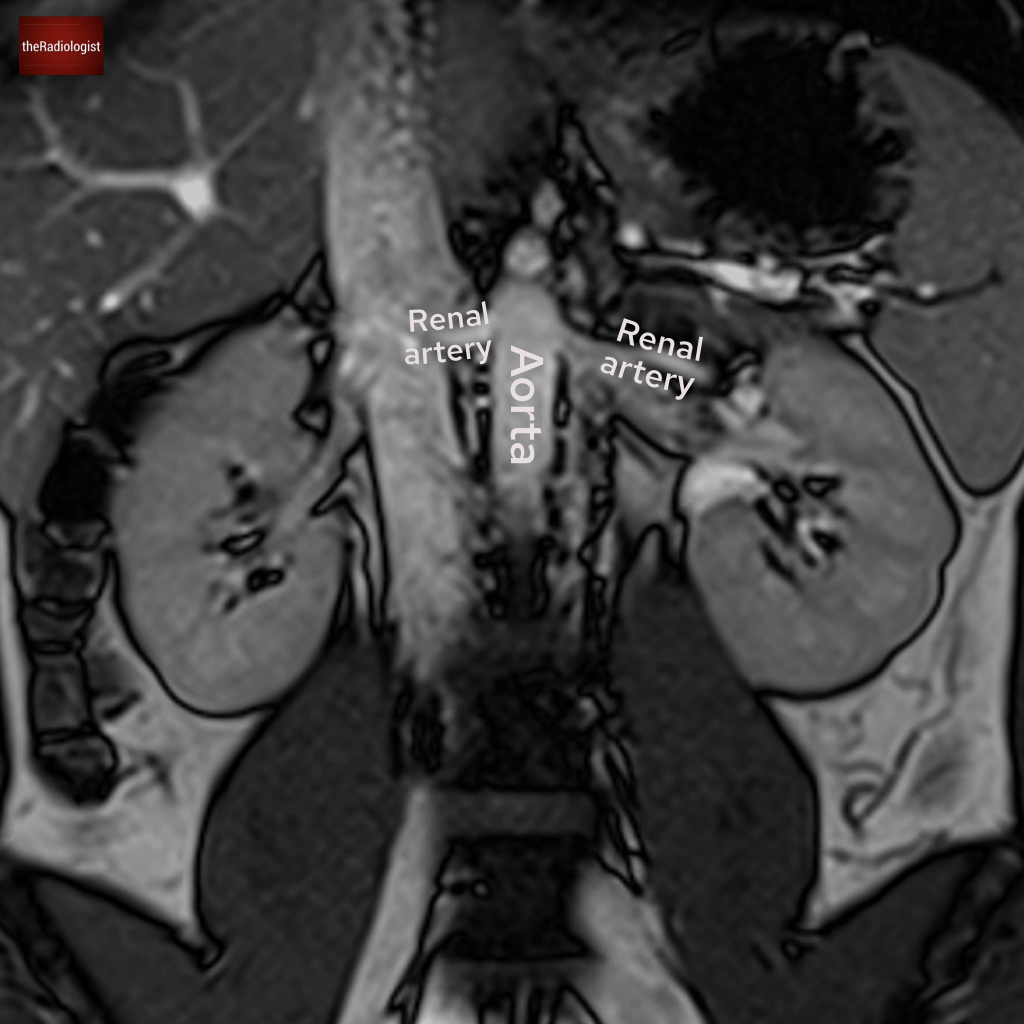

Now let’s look at an abdominal MRI. What is the arrow pointing at?

Choose from one of the following: